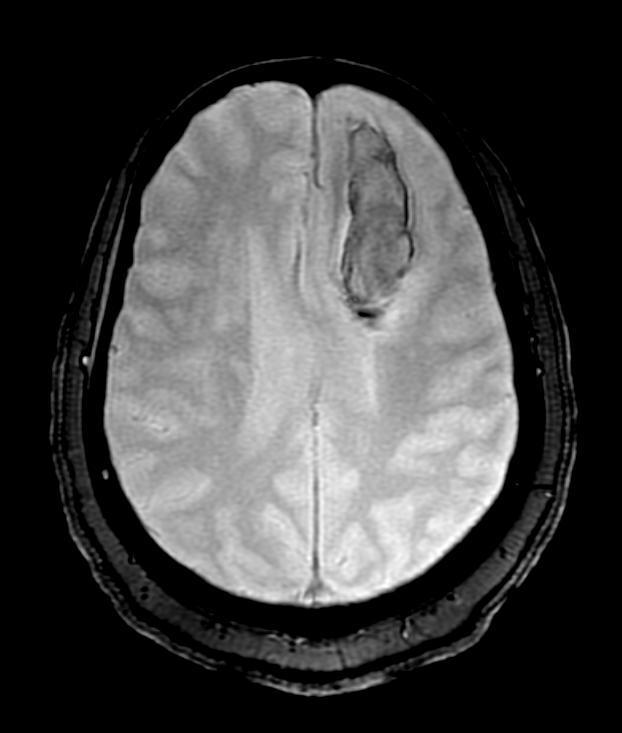

5 An early subacute hemorrhage is bright on a T1-weighted image (left) turning dark on a T2-weighted image (right).

Approximately three days after hemorrhage, the hematoma will begin to turn bright at the margins on T1-weighted images as deoxyhemoglobin is converted to methemoglobin. As long as the red cells are intact, however, this area will remain dark on T2-weighted images, because intracellular methemoglobin has a short T2 (figure 5). Both intracellular deoxyhemoglobin (acute hemorrhage) and intracellular methemoglobin (early subacute hemorrhage) appear dark because both have paramagnetic heme iron inside of the intact red cells. Because of this paramagnetism, the inside of the red cell becomes more magnetized than the nonparamagnetic plasma on the outside of the red cell. This leads to magnetic non-uniformity, which causes dephasing, or T2 shortening, and thus decreased signal on a T2-weighted image.